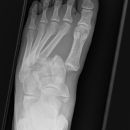

Lisfranc Luxationsfraktur